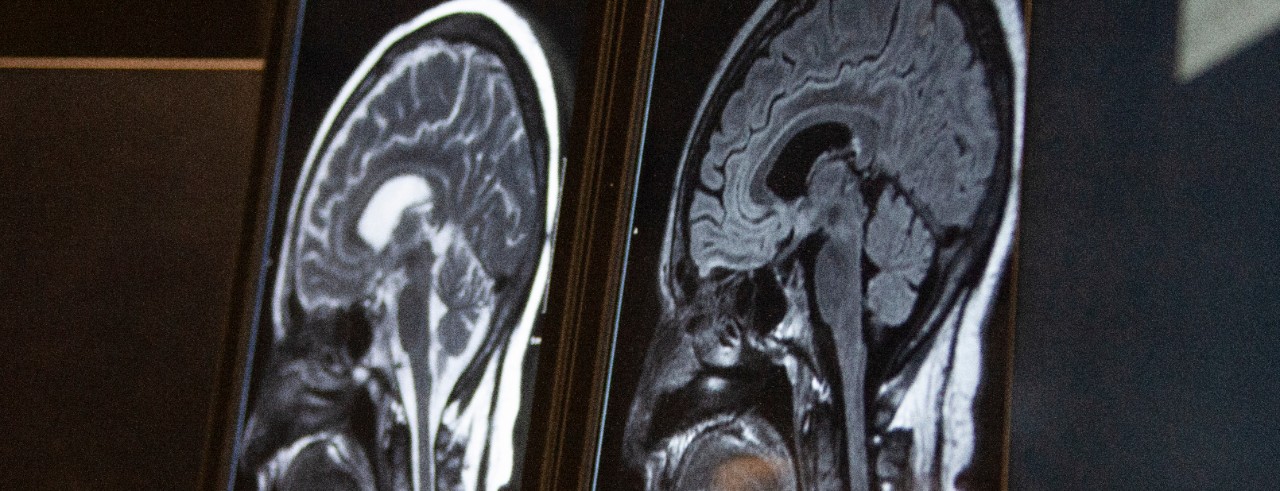

Featured photo at top of brain scans. Photo/Ravenna Rutledge/University of Cincinnati.